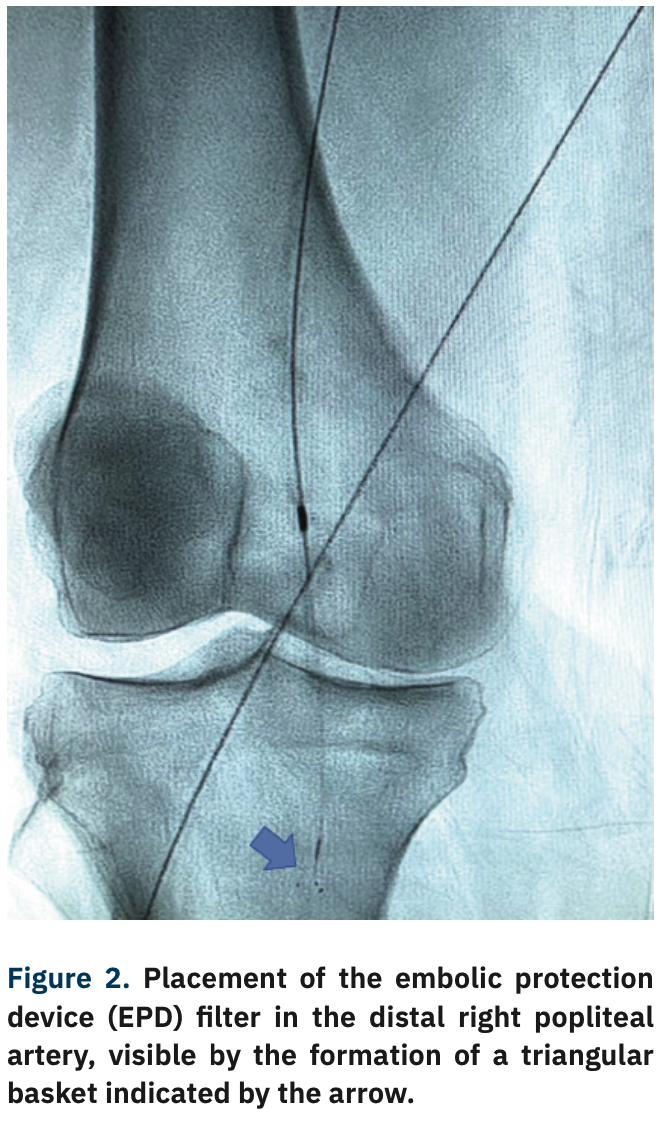

Contralateral retrograde access of the left femoral artery was obtained, and a 6 French (Fr) 45 cm sheath was advanced to the level of the right common femoral artery (CFA). A Mongo wire (Asahi Intecc) was inserted to cross the distal SFA and popliteal lesions. An embolic protection device (EPD) filter was placed in the distal popliteal artery (Figure 2). Orbital atherectomy was performed with a 1.5 solid crown Diamondback (CSI), followed by a 5 mm x 250 mm drug-coated balloon at the lesioned sites (Figure 3).